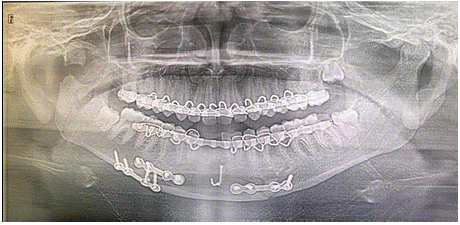

Patient was placed on intermaxillary fixation (IMF) for Angle fractures and condyle fracture. Patient had persistent swelling in front of the right ear since then. The patient reported to us for treatment of swelling on the right side of the face and also for the removal of IMF. Swelling was gradually increase in size, nontender and pulsatile in nature. CT- BRAIN angiography was advised to identify feeding vessels. CT-BRAIN angiography suggestive of heterogeneous lobulated lesion with hyperdense content of blood attenuation within, measuring 5x 3.8 x 5.4 cm (AP TRA CC) is seen involving the right masticator, parotid spaces and infratemporal fossa adjacent to right TMJ were performed findings are suggestive of post traumatic pseudoaneurysm formation with feeders from posterior auricular artery. The patient underwent additional imaging in the form of a carotid angiogram for detailed assessment of pseudoaneurysm which revealed an large pseudoaneurysm originating from internal maxillary artery.

Routine access through the femoral artery was obtained and a catheter was navigated to the common carotid artery. From this position, an angiogram was completed to survey details of size and location of aneurysm and the interventional radiologist team coiled the pseudoaneurysm for definitive management. Embolization was done through the microcatheters over microwire with 6 mm x 14 cm and 3 mm x 14 cm coils (Figure 2,3).

Figure 2: Before embolization.

Ater that patient is planned for excision of hematoma as well as also the open reduction and internal fixation for the ramus and angle fracture (Figure 4).